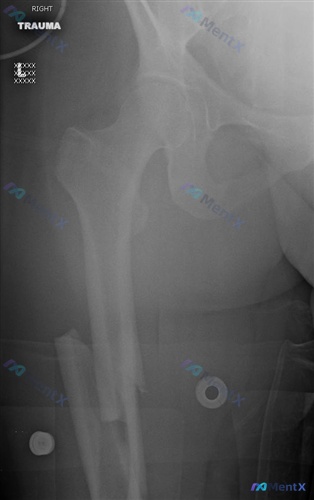

病例资料整理 患者信息:22 岁男性 主诉:股骨损伤 影像表现: - 右侧股骨干中上段粉碎性骨折,骨结构连续性中断 - 骨折断端明显移位及重叠,远端向近端移位,短缩畸形 - 近端股骨结构相对完整,未见关节内骨折线 - 可见金属外固定支架组件投影,处于外固定治疗状态 讨论焦点 这份病例资料涉及股骨干骨...

整理了一份昨天看到的股骨干骨折病例,关于手术入路的选择和并发症对比,觉得挺有代表性的,和大家分享一下思路。 --- 病例基本信息 - 患者:33岁女性 - 损伤类型:急性创伤(影像见图A) 影像核心表现(右侧大腿正位X光) 1. 骨折征象:右侧股骨干中下段可见明显骨皮质连续性中断,属于横断性骨折(伴...